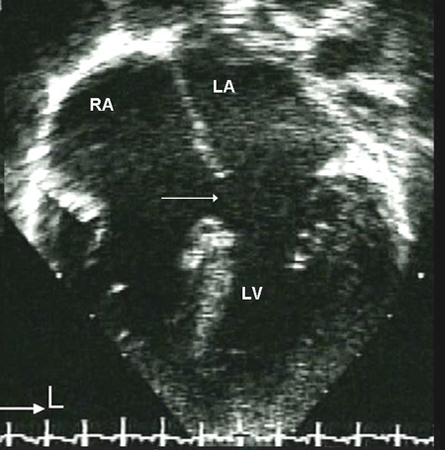

Os defeitos perimembranosos normalmente ocorrem como uma lesão solitária e, às vezes, podem fechar espontaneamente pela aposição do folheto septal da valva tricúspide ao defeito. Os defeitos de saída podem ser grandes e associados a formas mais complexas de cardiopatias congênitas, como a tetralogia de Fallot. Os DSVs de saída ou peri-membranosos estão intimamente próximos da cúspide direita da valva aórtica. Por causa do efeito Venturi, esses defeitos podem causar prolapso de uma cúspide da valva aórtica, o que resulta em uma restrição do fluxo através do DSV e regurgitação da valva aórtica.[22] Os defeitos de entrada não se fecham espontaneamente e podem estar associados com o defeito do septo atrioventricular (DSAV) e com a regurgitação da valva AV. Os defeitos musculares são os tipos mais comuns de DSVs em neonatos e a grande maioria fecha espontaneamente antes dos 2 anos de idade.[Figure caption and citation for the preceding image starts]: Imagem da ecografia apical de 4 câmaras de um defeito do septo ventricular (DSV) muscular (seta). (AD) átrio direito; (AE) átrio esquerdo; (VD) ventrículo direito; (VE) ventrículo esquerdoImagem cedida por Patrick W. O'Leary, MD [Citation ends].